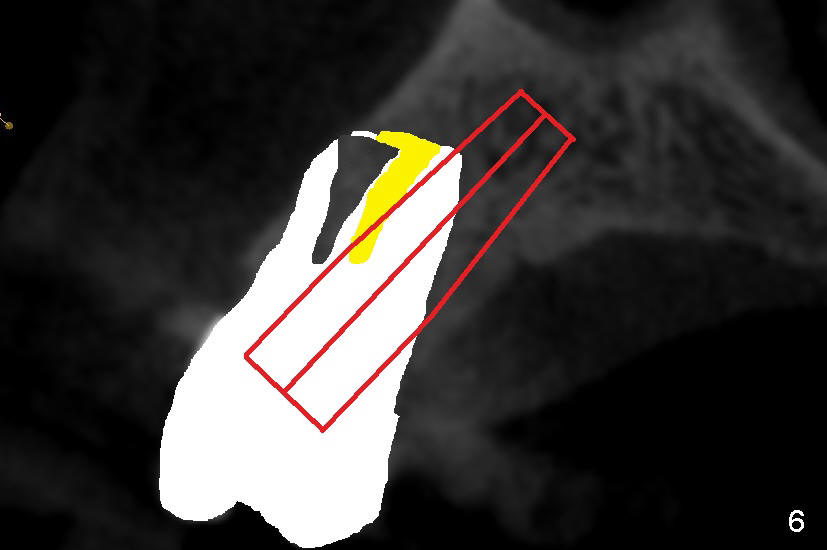

It is known that that buccal wall (apical) of anterior teeth including bicuspids is thin (Fig.1 between arrowheads). Fig.1 is a CT coronal section of an upper first bicuspid, whereas Fig.2 is a diagram showing after extraction. We are going to show how immediate implantation is to push the septum buccally (arrow) to close the buccal apical defect.

Even in a single root socket, osteotomy is to be created in the palatal wall. To get a "catch", a drill or osteotome (RT for example; Fig.3 pink line) is placed more or less perpendicular to the palatal wall. Once the catch is achieved, the axis of osteotomy is changed (Fig.3 curved arrow), more or less parallel to the bone morphology (buccal and/or palatal walls, Fig.4). Gradually the osteotomy is increased in diameter (Fig.5 pink area). In the single root, a separate, palatal socket has been created with formation of a septum. Subsequently, taps and the implant (tapered, Fig.6 red portion) will push the existing or just formed septum buccally (from yellow area to grey area). The fractured and displaced septum is going to participate in repairing the buccal apical defect if the pre-existing infection is under control under protocol proposed by Tatum group.